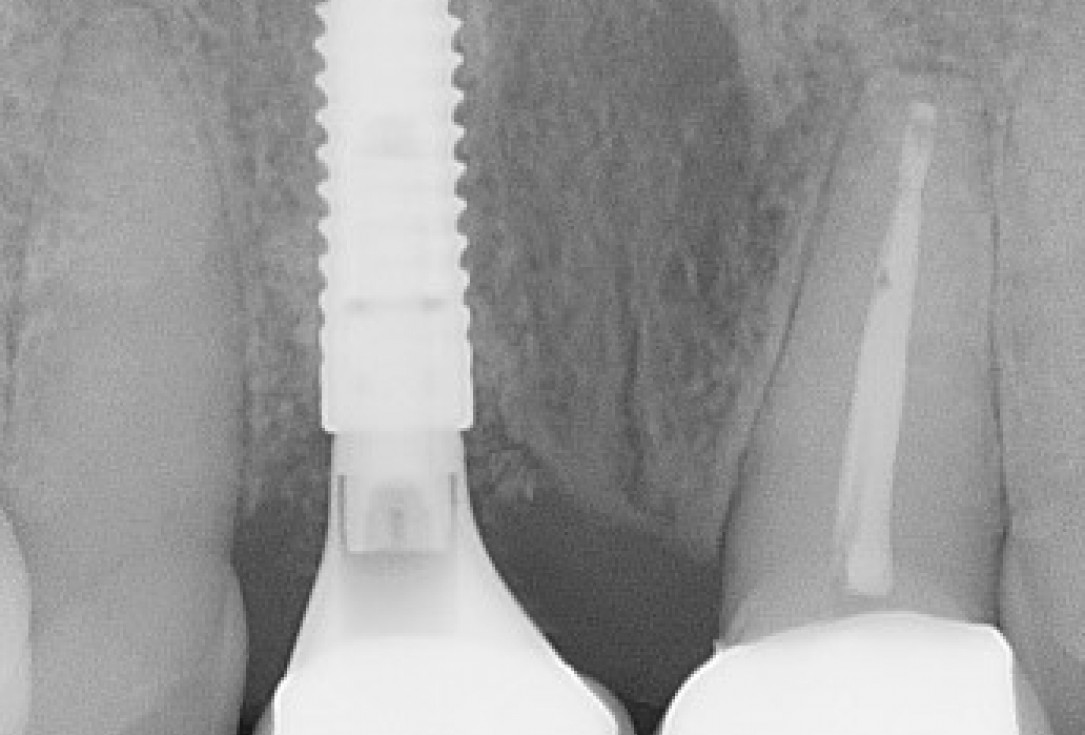

21/22 - Radiographs during therapy.Immediate implant placement and regeneration of ridge using an allograft bone ring and Jason® membrane - Drs. Miller and Korn

22/22 - Final radiograph one week post insertion.Immediate implant placement and regeneration of ridge using an allograft bone ring and Jason® membrane - Drs. Miller and Korn